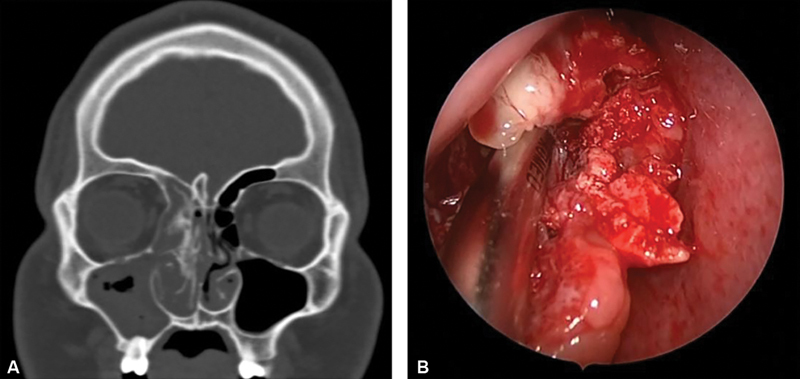

Objective: Chondro-osseous respiratory epithelial adenomatoid hamartoma (COREAH) is a rare benign growth within the nasal cavity or paranasal sinuses. We aim to highlight the pathogenesis and clinical presentation of an extremely rare benign mass within the nasal cavity and demonstrate the workup, diagnosis, and management of this rare lesion, as well as review the literature.

Methods: Retrospective review of a patient presenting with COREAH of the sinonasal cavity treated at a single tertiary academic medical center. The MEDLINE database was additionally searched for all case series or reports of sinonasal or skull base COREAH.

Results: A total of sixteen articles were identified for review. In addition to the current case, a total of nineteen patients were identified in literature found to have sinonasal or skull base COREAH. The most common primary sites of attachment were the lateral nasal wall and posterior septum. Only two cases were identified with skull base attachment. Computed topography (CT) was employed in 84.2% of patients, and CT with MRI was utilized in 26.3% of patients. Endoscopic resection was performed in 100% of patients, with one recurrence reported in the literature and one incomplete resection requiring revision surgery.

Conclusion: COREAH is an extremely rare hamartoma consisting of glandular proliferation with cartilaginous and osseous stroma. COREAH is symptomatic in 100% of reported cases in the literature, and complete surgical resection is often curative. Our case represents the longest follow-up reported with 4 years postoperatively revealing no growth or recurrence of COREAH.